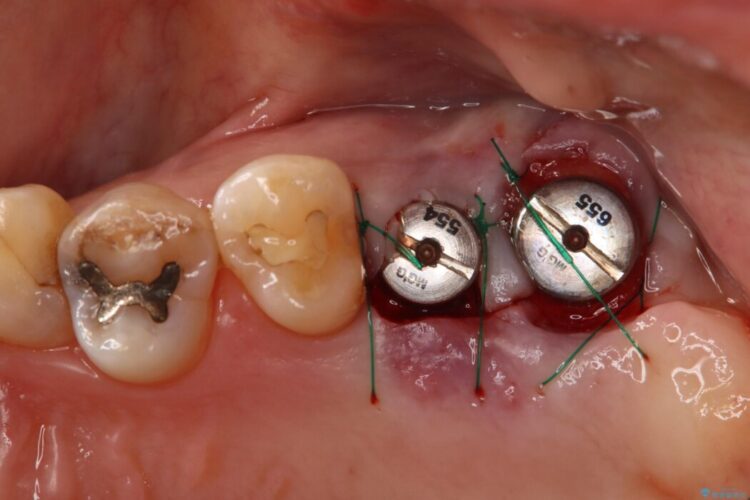

7番については抜歯と同時にインプラントを埋入する「抜歯即時埋入法」を選択。通院回数と治療期間を大幅にカットすることで患者様の負担を減らします。

あわせて6番目にもインプラントを行い、奥歯でしっかり力強く噛める状態を整える計画です。